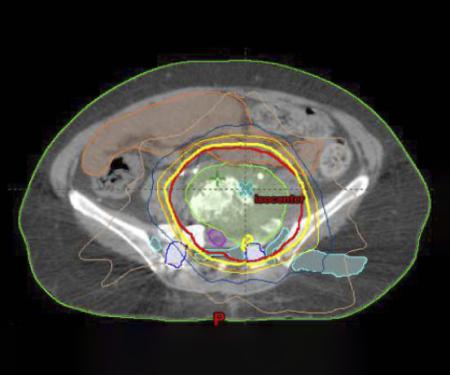

Stereotactic Body Radiation Therapy (SBRT), Intensity Modulated Radiation Therapy (IMRT), Image-Guided Radiation Therapy (IGRT), Radioembolization, MR-guided Focused Ultrasound, Re-irradiation, Pulsed Low Dose Rate (PLDR) radiation, Brachytherapy, Anal Cancer